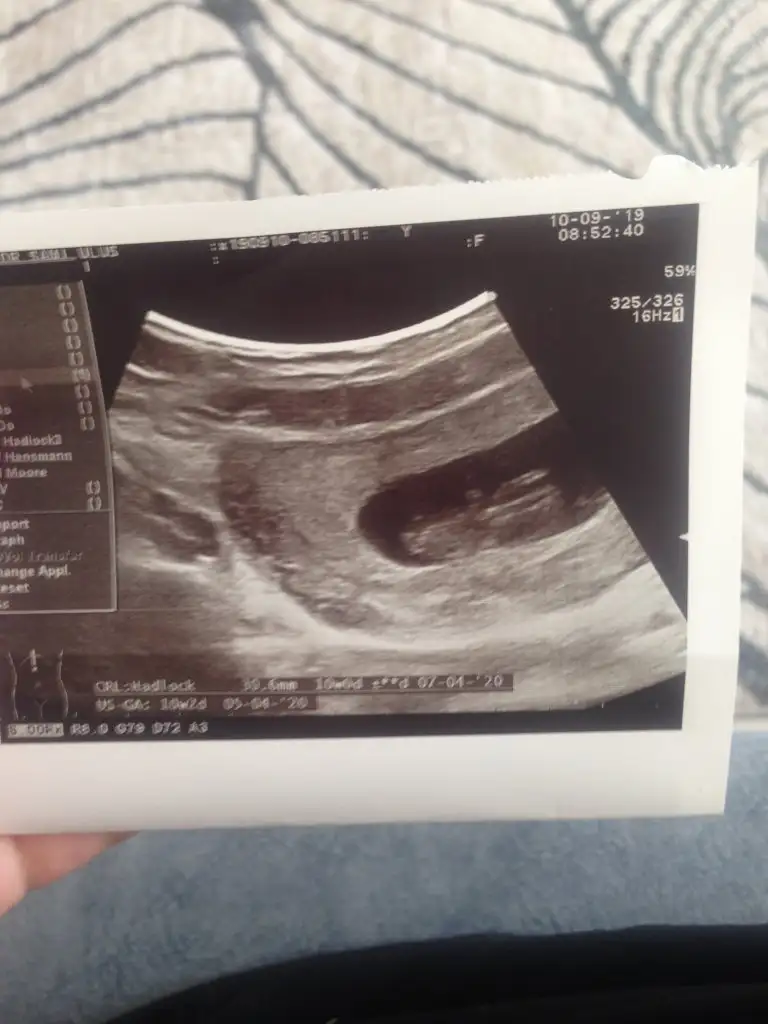

Daha netini çekebilirsem paylasacagim tekrar :) Doktorda bacak arasinda bir sey goremedim ama bidahakine belli olur dedi. Ultrasonda 12 haftalik cikiyor ama regl tarihime gore 10+5Kıza gibi net usg yokmu çok net degil kaç haftalık 11 yada 12 olmalı

14+ 5 de nub olmaz 11 yada 12 haftanda nub kızdı tahminimArkadaşlar merhaba 14 haftalık ultrasona yorum yaparmısınız